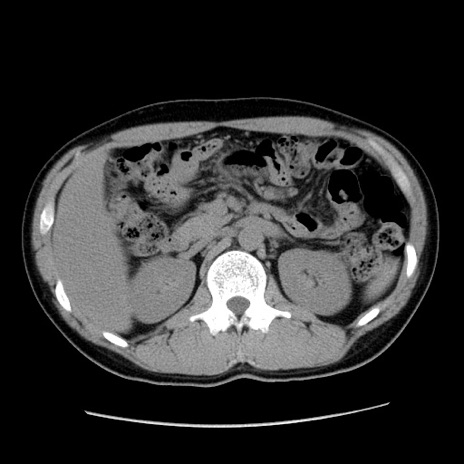

症例36(横断像)

【症例】20歳代 男性

【主訴】心窩部痛

【現病歴】今朝より上腹部痛あり。一旦軽快していたが再度出現したため救急要請。昨日夕に白身の魚を含む刺身を食べた。

【身体所見】BP 136/89mmHg、HR 74/min、BT 37.0℃、腹部:膨満、軟、心窩部に圧痛あり。反跳痛なし、筋性防御なし、腸雑音やや亢進あり。

【データ】WBC 17700、CRP 0.48